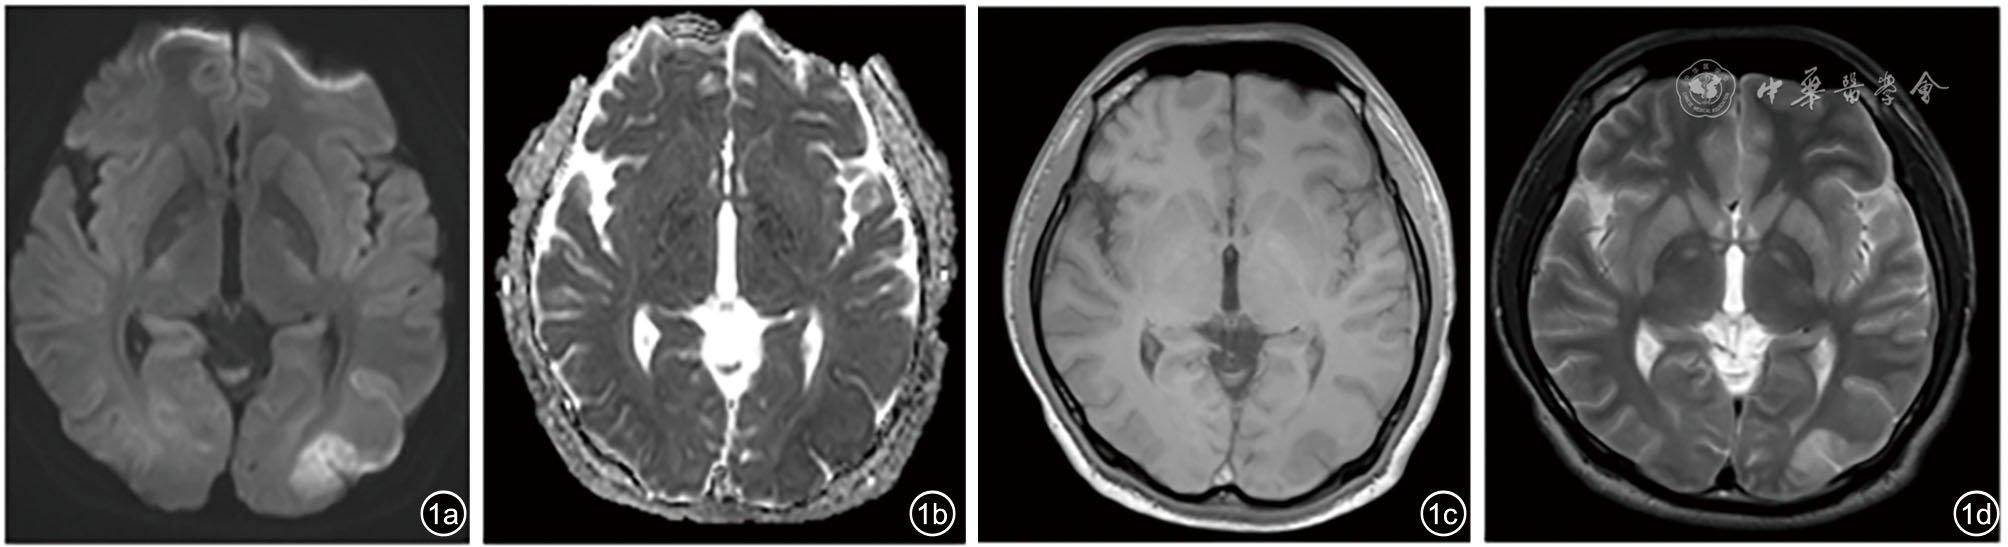

图1 患者头颅MRI示两侧顶枕叶见片状弥散加权成像高信号(图a)、表观扩散系数等低信号(图b)、T1加权成像稍低信号(图c)、T2加权成像高信号(图d)病灶,大多位于皮质区,胼胝体压部、基底节区各深部核团见类似信号灶,结合病史,考虑缺血缺氧性脑病